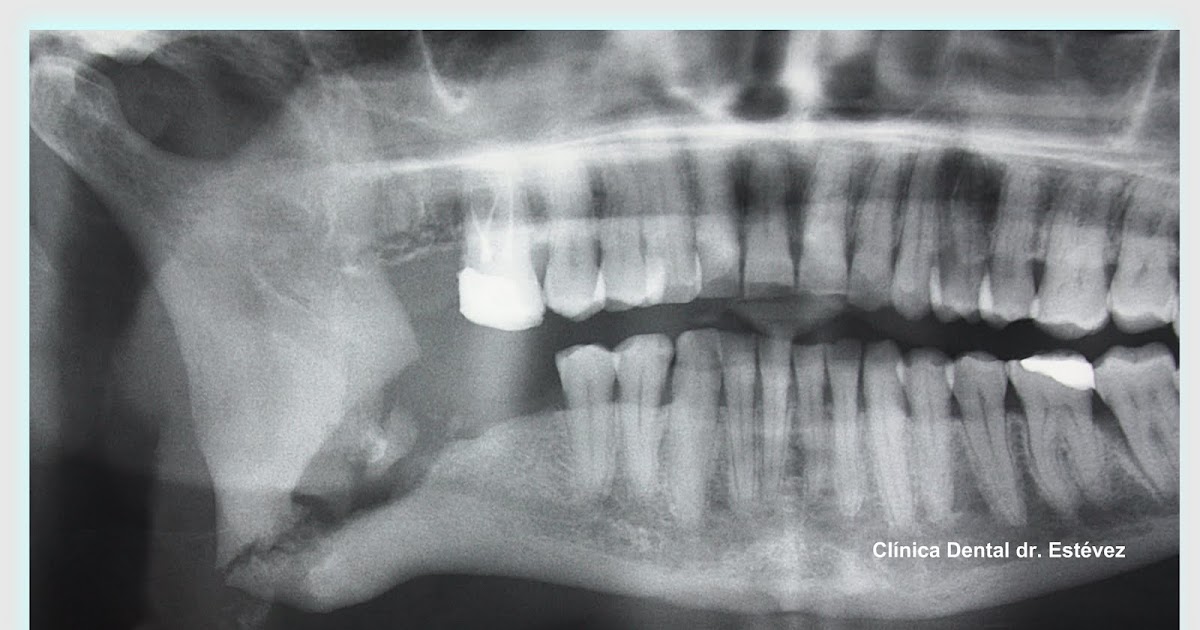

Panoramic dental Xray showing right mandibular osteomyelitis (“lumpy

From drestevez.blogspot.com

Clínica Dental Madrid Dr. Estévez Osteomielitis del maxilar inferior Dental Osteomyelitis osteomyelitis is an infection in a bone. Bacterial osteomyelitis of the jaw is a severe disease potentially requiring extensive surgical treatment. It may be acute or chronic. Infections can reach a bone by traveling through the bloodstream or. osteomyelitis of the jaws following dental treatment is a rare condition which usually occurs in immuno. osteomyelitis of the. Dental Osteomyelitis.

Panoramic dental Xray showing right mandibular osteomyelitis (“lumpy Dental Osteomyelitis It may be acute or chronic. osteomyelitis is an infection in a bone. A definitive diagnosis of osteomyelitis can only be made via bone biopsy. Bacterial osteomyelitis of the jaw is a severe disease potentially requiring extensive surgical treatment. Osteomyelitis of the jaws is predominantly a disease of the mandible, whereas the maxilla by virtue of its vascularity and. Dental Osteomyelitis.